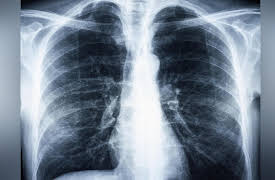

Cough, Cough, Cough